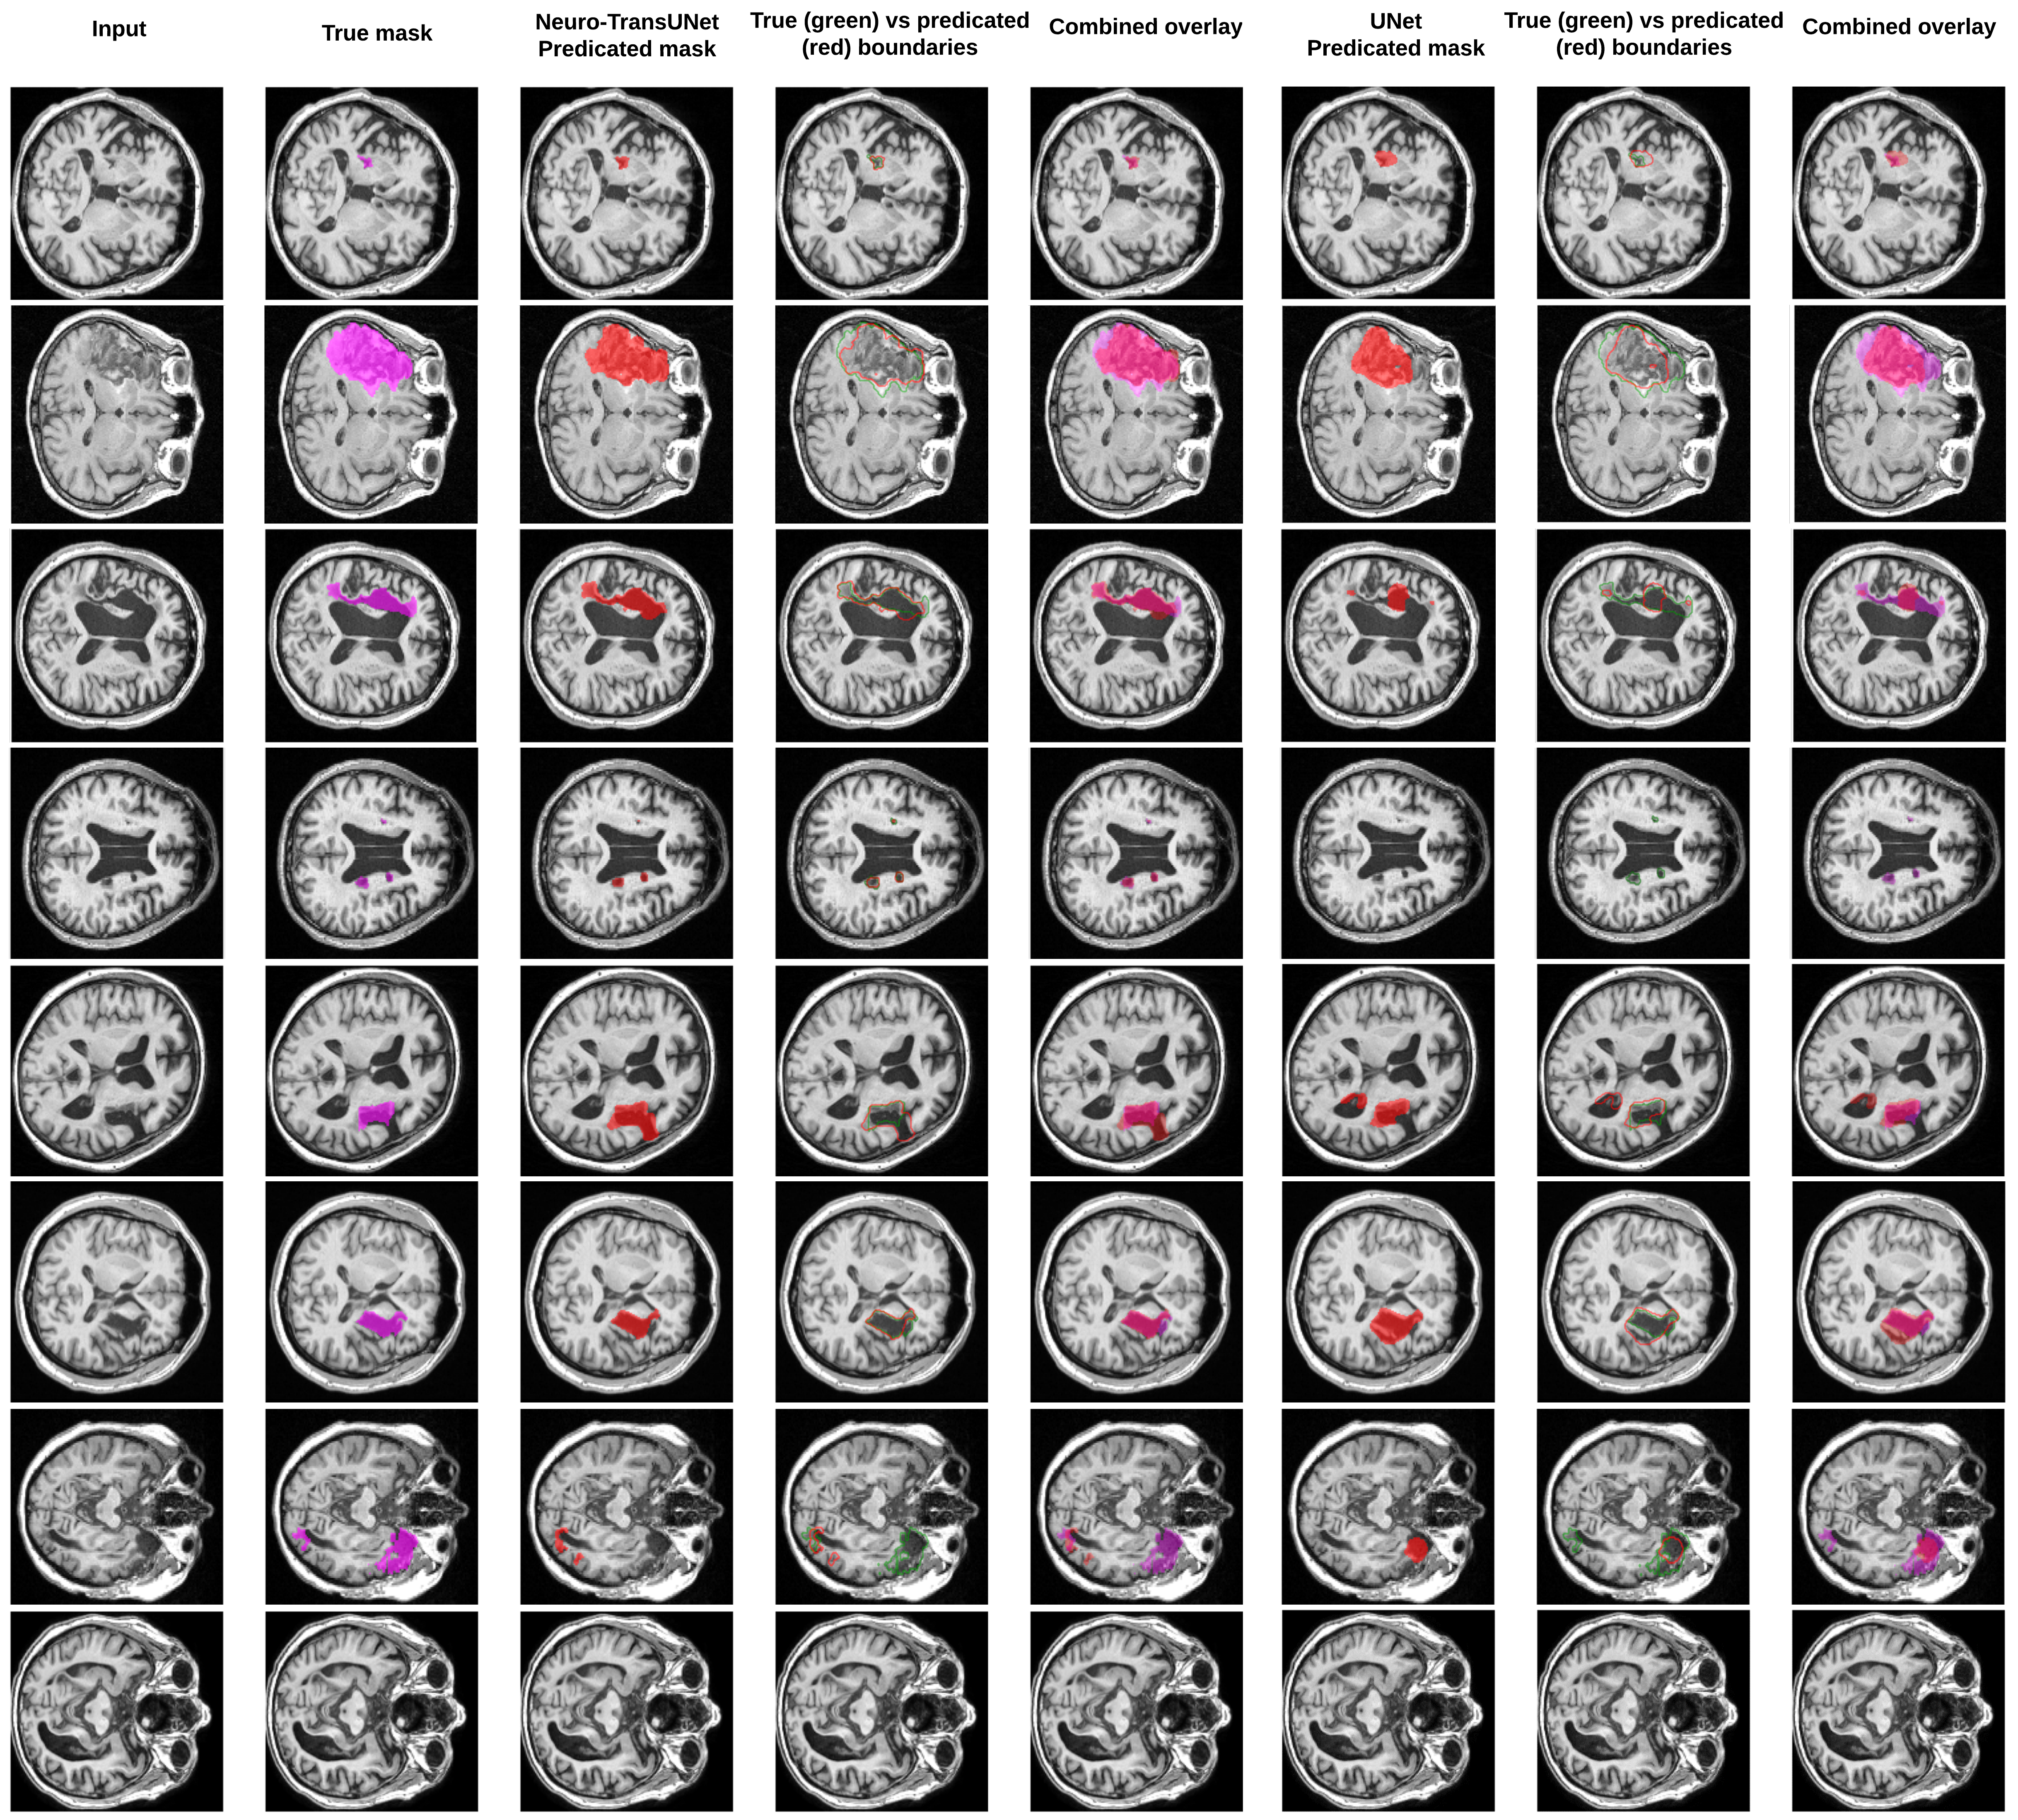

Refer to caption

Figure 6: Visualization depicts a systematic evaluation of Neuro-TransUNet’s performance on MRI. Each row has a different patient case and a flow that starts with the MRI, goes to the ground truth, the predicated mask overlay by Neuro-TransUNet, a comparison of true versus predicted boundaries, and ends with an overlay of all the elements. The following right side shows the model-predicated masks without SwinUNETR, a comparison of predicted boundaries, and a combined overlay. It also emphasizes the improvements made by incorporating SwinUNETR into the Neuro-TransUNet model. The visualizations display a range of lesion presentations, ranging from small to numerous lesions, including subjects with no lesions to those with multiple lesion occurrences.

The precision of the Neuro-TransUNet model in segmenting small, large, and multiple lesions is good, as it has shown a close match with the annotations of experts. Such correspondence suggests that the model can detect clinically different changes in the neuropathological state. The model has demonstrated the ability to precisely locate small lesions, which are more difficult to detect than larger lesions due to their low contrast and signal-to-noise ratio. The model’s specificity stands out in lesion-free subjects, a particularly essential factor used in the prevention of false positives and in avoiding the risk of wrong diagnosis. Furthermore, the model can correctly identify multiple lesions that might be present in a single case, which is necessary for a complete evaluation of the stroke lesions. The visualization results also reveal the effectiveness of integrating SwinUNETR into the proposed model. The SwinUNETR, which provides global context, significantly enhances the segmentation of lesions. In cases with multiple lesions, the proposed Neuro-TransUNet model also yields better accuracy in segmenting the lesions. This improved performance highlights the importance of incorporating SwinUNETR into more advanced fusion and segmentation synergistic approaches for better lesion identification in complex medical images. In the quantitative metrics, U-Net shows the optimal dice score of 0.633, a 13.29% decrease compared to the proposed model. The HD95 also decreased from 18.70 to 23.74, demonstrating the efficacy of incorporating SwinUNETR to improve model performance. The proposed model tends to have technical limitations when delineating lesions with non-distinct edges or non-standard diffusion patterns, where the segmentation may unconsciously underestimate the actual size of the lesion. In these situations, the segmentation scenarios may deviate from the reality of the task of distinguishing pathological tissue from the brain’s natural textural background. Such deviations, on the other hand, point out that the algorithmic interpretation of the same brain lesions is closely tied to their complex morphological profiles, indicating room for model improvement. The emergence of the above complexity implies a demand for larger data sets to train with more paths of pathological variants. The inclusion of more data with multiple modalities and potentially unusual appearances can improve the model’s learning process. Sophisticated training would help Neuro-TransUNet become acquainted with the unpredictable variability in medical imaging, allowing it to generalize more effectively. This will bring about more precise segmentation outputs that can precisely depict the complexities of cerebral abnormalities.